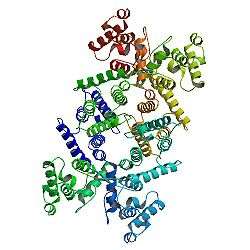

Dystrophin protein is found in muscle fibre membrane; its helical nature allows it to act like a spring or shock absorber. Dystrophin links actin in the cytoskeleton and dystroglycans of the muscle cell plasma membrane, known as the sarcolemma (extracellular). In addition to mechanical stabilization, dystrophin also regulates calcium levels.[6][7]

Dystrophin is part of a complex structure involving several other protein components. The "dystrophin-glycoprotein complex" helps anchor the structural skeleton (cytoskeleton) within the muscle cells, through the outer membrane (sarcolemma) of each cell, to the tissue framework (extracellular matrix) that surrounds each cell. Due to defects in this assembly, contraction of the muscle leads to disruption of the outer membrane of the muscle cells and eventual weakening and wasting of the muscle.[9] |